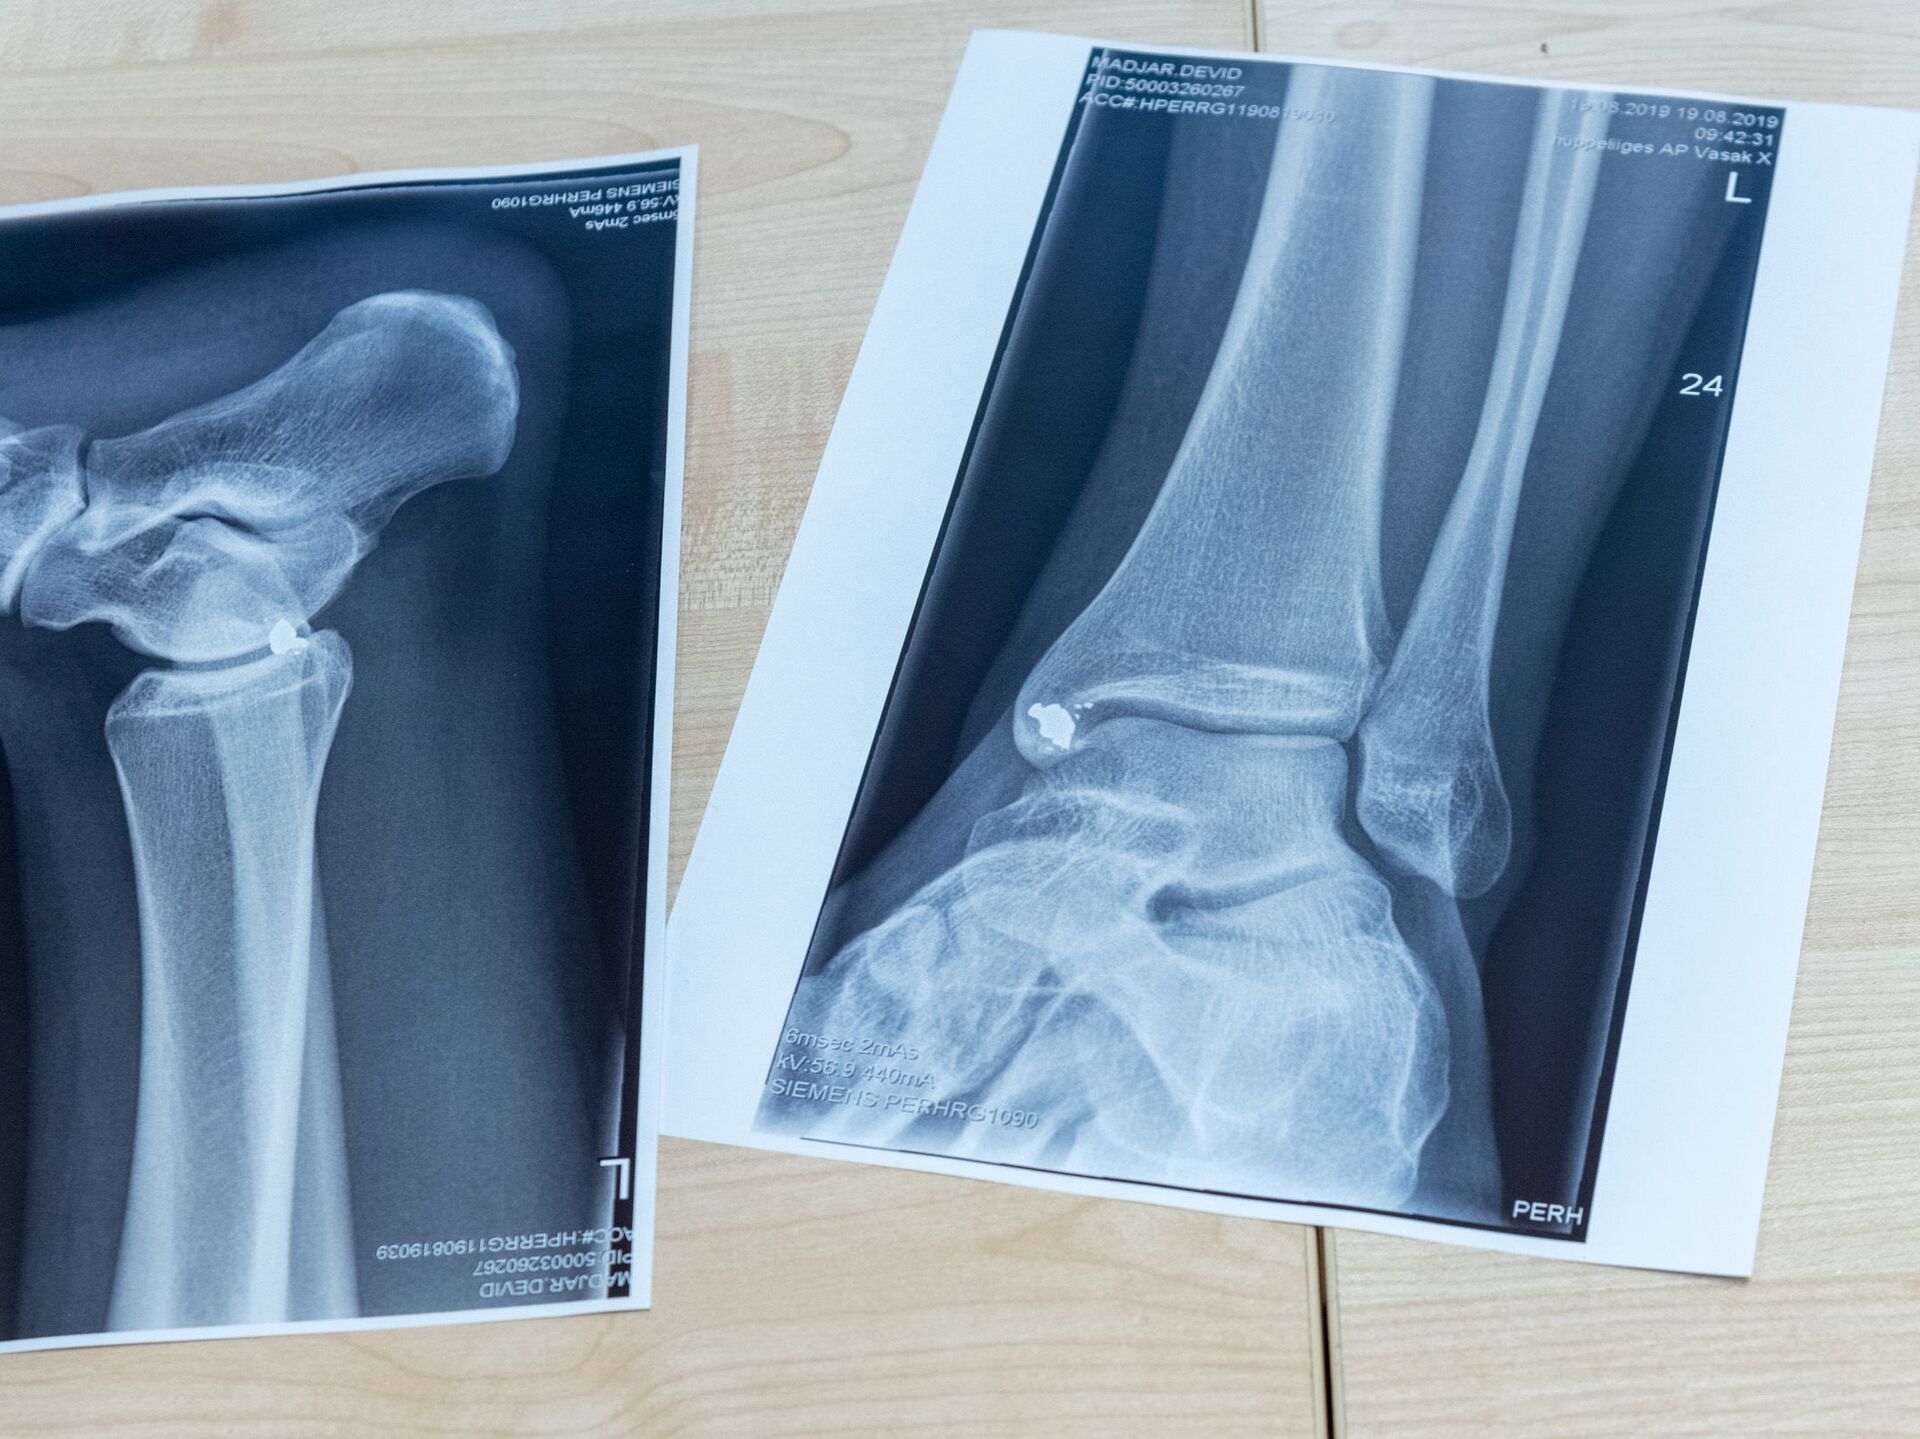

РИГА, 17 апр - Sputnik. В феврале этого года Екабпилсская больница получила жалобы на некачественную работу двух врачей-травматологов и приостановила работу отделения травматологии. Сейчас экстренную помощь пациентам оказывают помощники врачей или хирурги, а в более сложных случаях людей переводят в другие стационары - чаще всего в Мадону.

Больница объявила набор сразу на несколько вакансий: заведующего отделением травматологии, травматолога, ортопеда и дежурного травматолога. Медикам предлагают около шести тысяч евро брутто, а также возможность работать на неполную ставку. Но желающих пока нет.

Как отметил заместитель председателя думы Екабпилсского края по вопросам здравоохранения Айварс Ванагс, поиск травматологов напоминает "поиск иголки в стоге сена". Единственный кандидат хотел зарплату в 15 тысяч евро.

Если в течение ближайших двух месяцев специалистов найти не удастся, местные власти намерены начать переговоры с министерством здравоохранения о дальнейших шагах. Один из возможных сценариев - полное закрытие отделения до появления новых врачей.